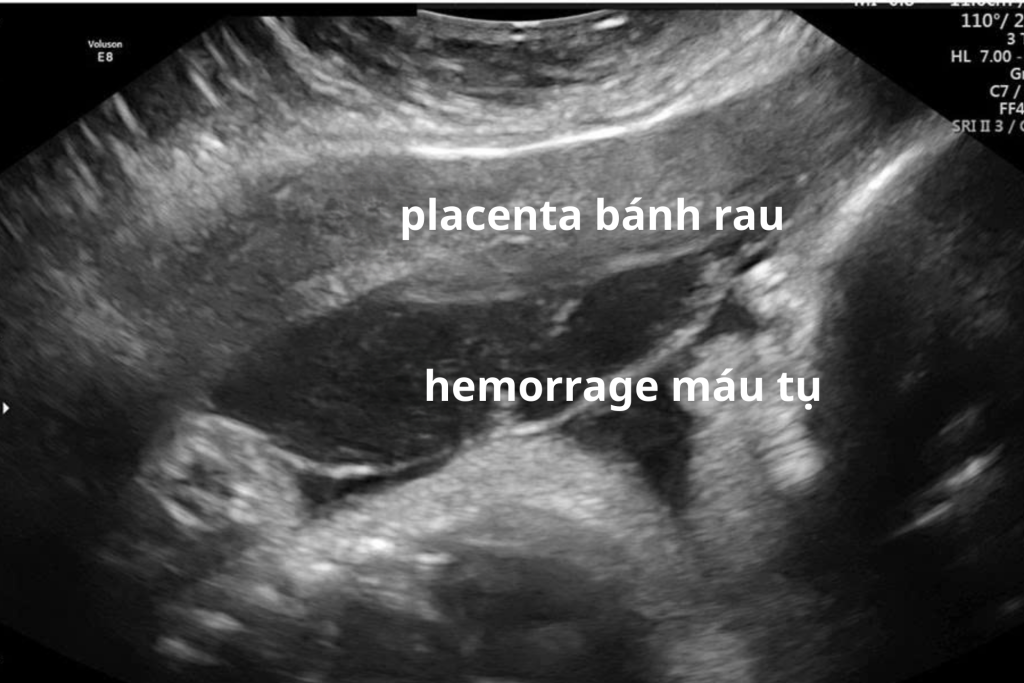

Nhau bong non là tình trạng bánh nhau tách khỏi thành tử cung trước khi thai được sinh ra.

- Có thể hình thành khối máu tụ phía sau bánh nhau

Trên siêu âm, bác sĩ có thể thấy:

- Khối máu tụ sau bánh nhau

- Vùng giảm âm bất thường

- Bất thường cấu trúc bánh nhau